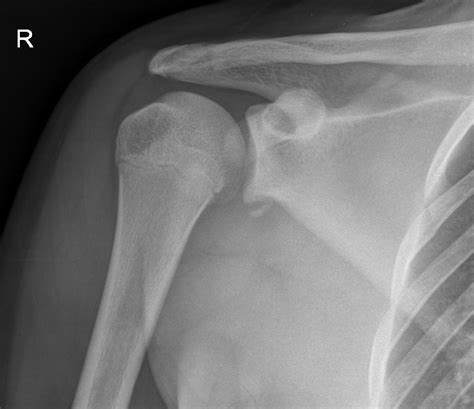

• X-rays: These can help identify fractures and dislocations but may not always show the Hill Sachs lesion clearly.

Diagnosing a Hill Sachs Fracture involves a combination of physical examination and imaging tests. The diagnostic process typically includes:

A Hill Sachs Fracture is a specific type of injury that occurs in the shoulder joint. It involves a compression fracture of the humeral head, which is the upper part of the arm bone that fits into the shoulder socket. This fracture typically results from a dislocation of the shoulder, where the humeral head is forced out of its socket and then impacts the glenoid rim, causing a depression or fracture on the humeral head.